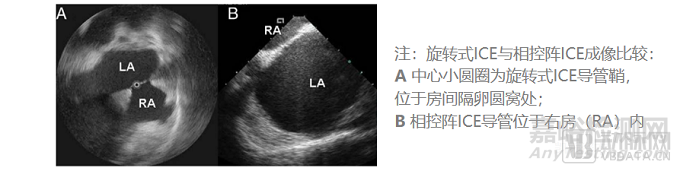

ICE使用5~12MHz的超聲頻率,理論最高分辨率可以達到0.1mm、且同時具有最高16cm的心內(nèi)穿透成像深度。常見的2D ICE導(dǎo)管分為單陣元旋轉(zhuǎn)超聲導(dǎo)管、電子相控陣列超聲導(dǎo)管兩類,目前后者在臨床上更為常用。目前ICE導(dǎo)管直徑為8~10Fr。

就2D ICE來說,相控陣ICE相比單陣元旋轉(zhuǎn)ICE具有以下優(yōu)勢:更深成像深度、獲取多普勒血流彩超的能力。相控陣ICE因而在2D ICE當(dāng)中更受青睞。